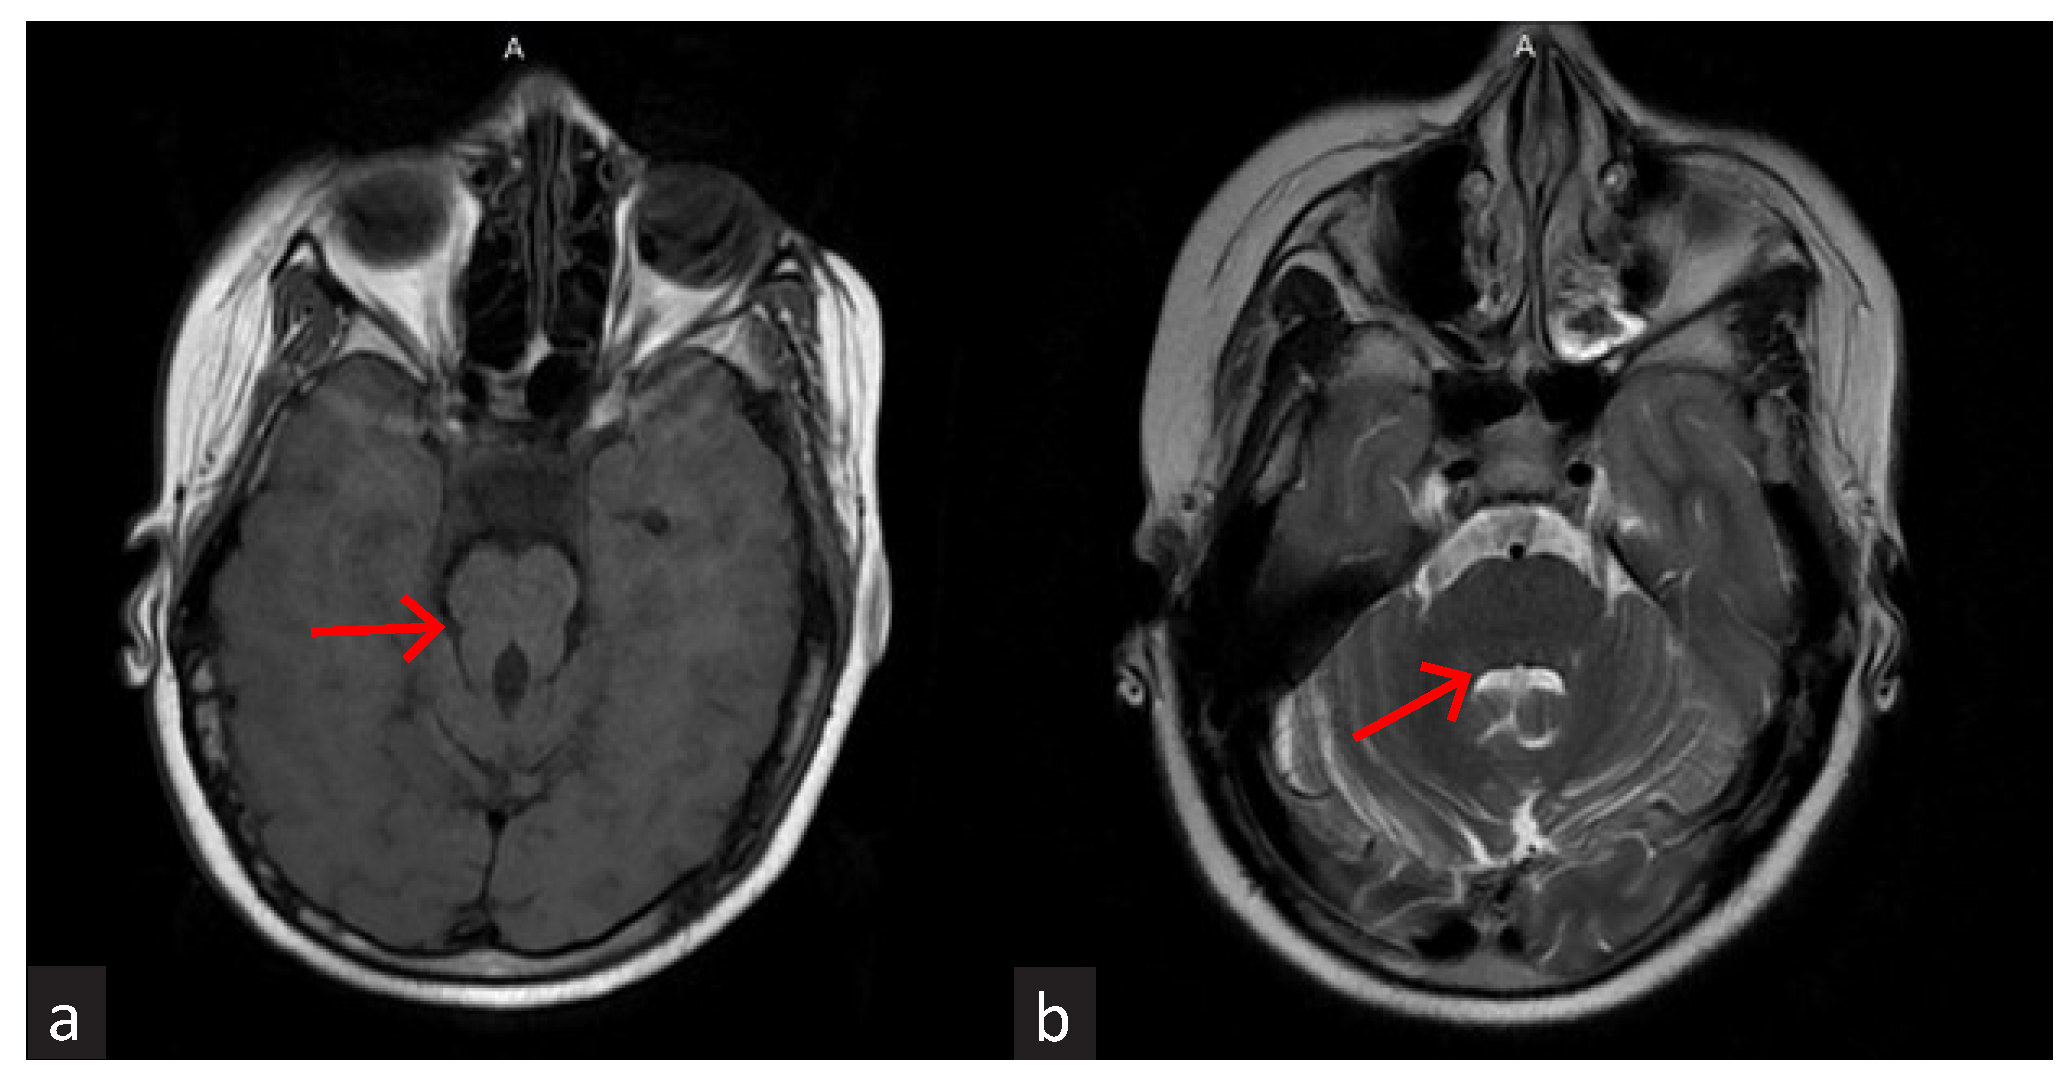

M K Hari Prasad, Renju Binoy, Himanshu Sekhar Mahapatra, D Akshay